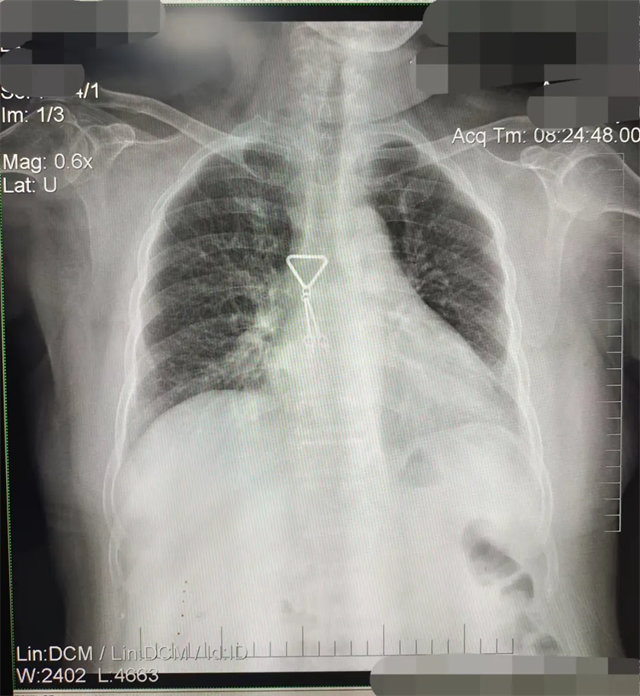

缺陷:左肩胛骨部分與左肺野重疊。

解決:使患者左肩旋前緊貼成像件重新曝光。